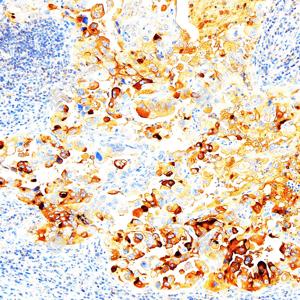

IHC检测CA125/MUC16蛋白(货号 GB15017). 样品: 人卵巢癌, 4%多聚甲醛 (货号G1101) 固定12-24小时. 抗原修复: 柠檬酸抗原修复液(干粉, pH 6.0) (G1201), 高压锅均匀喷气计时2分钟. —抗: 1: 500稀释, 4℃ 孵育过夜. 二抗: S-vision免疫组化多聚二抗(山羊抗小鼠), 即用型(货号G1301), 室温孵育20分钟. |